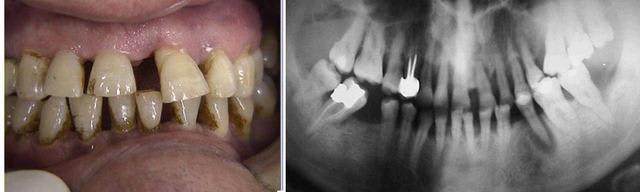

Au vu de la Pano.

ce cas présente

une alvéolyse horizontale (sous réserve de sondage)

pas de dents à intruser,

donc pas de risque de fabrication de poches avec accélération de destruction osseuse

avec environ 30% de perte osseuse dans le sens vertical, ce qui fait en surface radiculaire développée environ 50%

donc des dents facilement déplaçables

avec toutes ces réserves, on peut effectivement s’arrêter au 1°) des 5 étapes

Admettons donc que les problèmes infectieux de cet homme de 58 ans soient résolus (on peut toujours rêver, n’est-ce pas ?).

Au vu de ces :

« > destruction osseuse ancienne

> alvéolyse verticale et horizontale

> avec des poches infra-osseuses »,

- Penses-tu qu’il serait envisageable de faire un traitement ODF ?